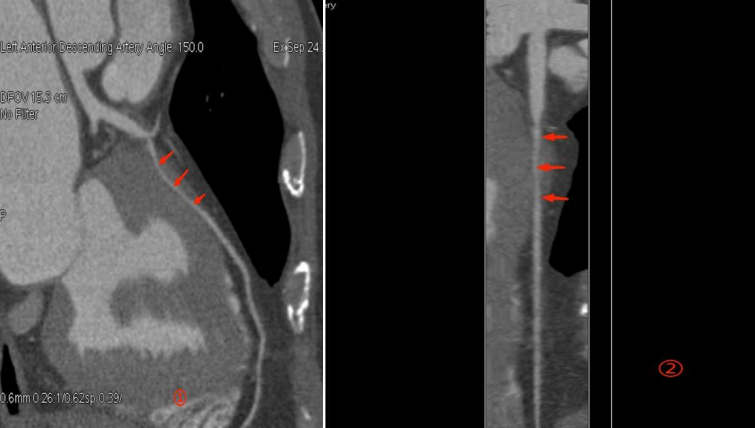

直到他接受我院双源CT冠状动脉CTA检查,真相才水落石出。图像清晰显示,他的左前降支中段(一支关键的心脏供血动脉)有一段走行于心肌纤维之下。在心脏舒张期,这段血管看似正常;但在心脏收缩期,这段血管被上方的心肌明显挤压、变窄——典型的“心肌桥”。

正是这个藏在心肌里的“桥”,在运动时随着心跳加剧而强力收缩,压迫冠状动脉,导致心肌暂时性缺血,引发胸闷胸痛。明确诊断后,医生为他制定了针对性的药物治疗和运动方案,症状得到有效控制,避免了病情的进一步发展与误判。

(↑ 冠状动脉CTA影像)